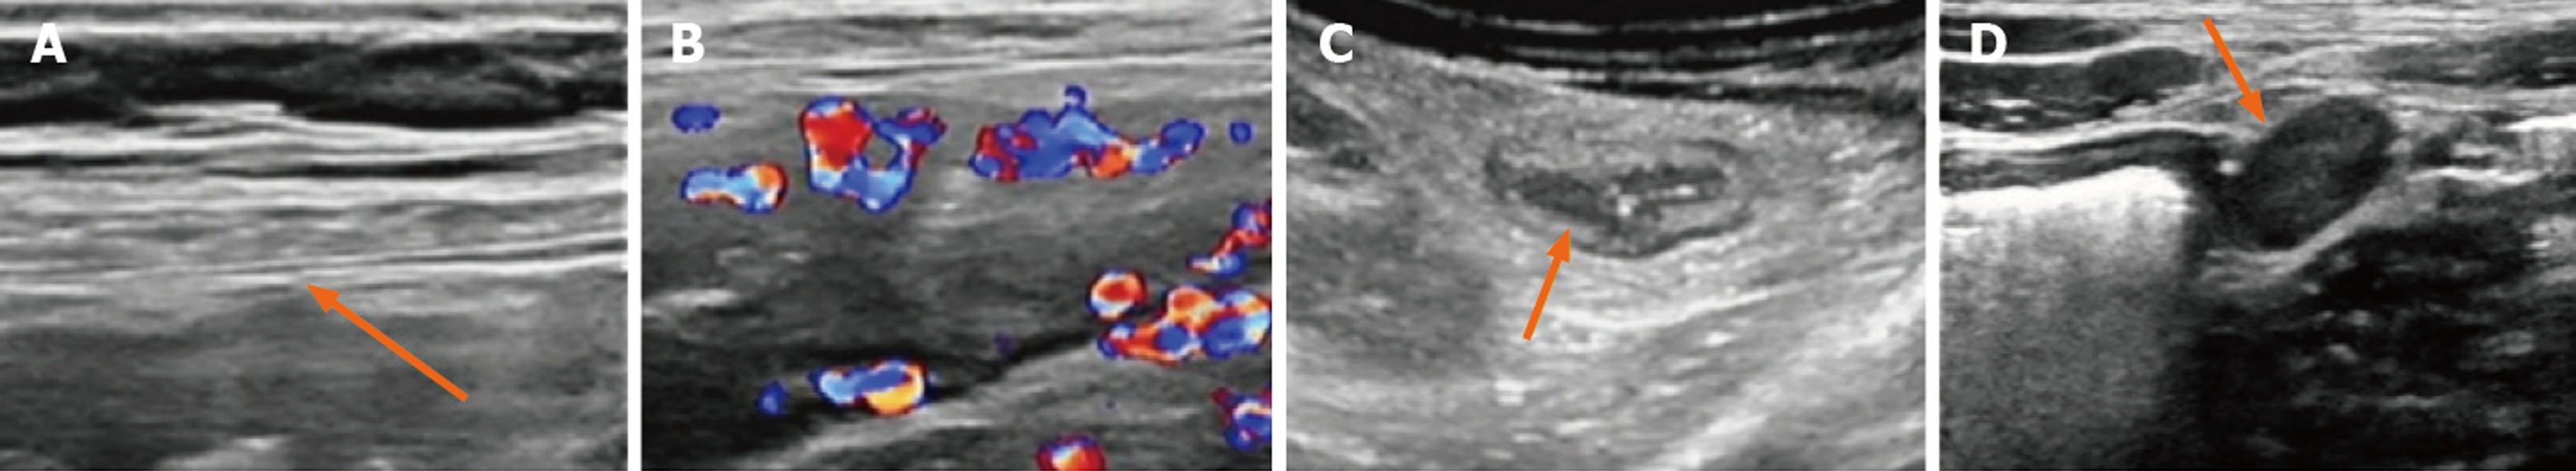

IUS的临床应用需遵循标准化操作规范与评估标准. 嘱患者检查前空腹4-6 h, 无需口服泻药、清洁灌肠等特殊肠道准备. 检查时遵循"从远及近"原则, 从直肠-乙状结肠开始, 依次系统扫查降结肠、结肠脾曲、横结肠、结肠肝曲、升结肠, 最终至回肠末段[9]. IUS评估UC的核心参数包括肠壁厚度(bowel wall thickness, BWT)、彩色多普勒信号(color Doppler signal, CDS)、肠壁分层及肠系膜脂肪增生, 同时可辅助评估是否存在肠系膜周围淋巴结肿大[10,11]. 内镜活动[Mayo内镜评分(Mayo endoscopic score, MES)2-3分]UC患者超声表现见图1. 当前被广泛国内外共识采纳的肠壁增厚判定标准为成人BWT>3.0 mm[12]、儿童BWT>2.0 mm[13]. 这一指标可作为肠道存在炎症的影像学提示. 肠壁增厚程度与UC病变程度呈正相关[14]. 最近陈宏桢等[15]的研究发现BWT是识别内镜活动最准确的IUS参数, 最佳诊断截断值为3.45 mm, 灵敏度为93.9%, 特异度为100.0%. 考虑现有研究得出的BWT阈值存在差异或与部分研究仅纳入病变最重肠段、部分研究纳入全结肠进行测量有关. 现血流信号常采用改良Limberg CDS评分, 该评分将血流信号分为0-3级: 0级为肠壁增厚, 但无异常血流信号; 1级为肠壁增厚, 见点状或短条状血流信号; 2级为肠壁增厚且可见>1 cm的长条状血流信号; 3级为肠壁增厚且出现与肠系膜相连的长条状血流信号. 通常认为改良Limberg CDS评分2-3级为UC疾病活动表现[16]. 正常肠壁结构在UC活动期出现模糊或消失, 这一现象的出现与UC疾病活动相关. 肠系膜脂肪增生表现为肠系膜肥厚、回声增高、脂肪包裹范围增加, 提示慢性炎症持续, 与UC复发风险相关[17]. 现有国内研究多为单中心、小样本探索, 且主要集中于单一指标的验证, 针对彩色多普勒评分、肠壁分层、肠系膜脂肪增生等多参数联合应用的系统性研究不足, 尚缺乏大样本、多中心、本土化的临床证据.